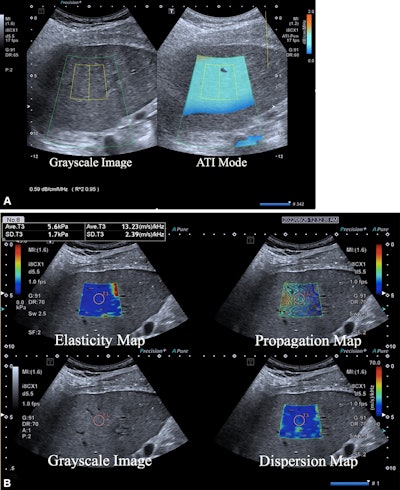

Multiparametric ultrasound in a 52-year-old female patient with metabolic dysfunction-associated fatty liver disease (MAFLD) and hepatitis B, whose body mass index was 26.9. (A) Gray-scale image (left) shows the liver parenchyma,

and attenuation image (right) shows the right liver lobe acquired from the right intercostal oblique plane, with the degree of attenuation color-coded in the sampling box. Orange indicates a high attenuation coefficient and blue indicates a low attenuation coefficient. The coefficient value (0.59 dB/cm/MHz) and reliability index (R2 = 0.95) are presented in the lower left corner. (B) 2D shear-wave elastography-generated quad-view mode image shows an elasticity map, propagation map, gray-scale image, and dispersion map at the same time. A 1-cm region of interest is placed within the sampling box of each image. Red and blue indicate high and low elasticity and dispersion slope, respectively. Liver stiffness on the elasticity map is 5.6 kPa, and the dispersion slope on the dispersion map is 13.23 (m/sec)/kHz. Image courtesy of the RSNA.